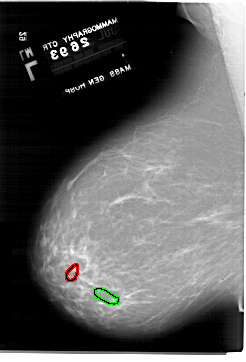

A_1918_1.LEFT_CC

LEFT_CC LINES 6511 PIXELS_PER_LINE 4996 BITS_PER_PIXEL 12 RESOLUTION 43.5 OVERLAY

FILE: A_1918_1.LEFT_CC.OVERLAY

TOTAL_ABNORMALITIES 1

ABNORMALITY 1

LESION_TYPE CALCIFICATION TYPE PLEOMORPHIC DISTRIBUTION CLUSTERED

ASSESSMENT 4

SUBTLETY 2

PATHOLOGY BENIGN

TOTAL_OUTLINES 1

BOUNDARY

ABNORMALITY 2